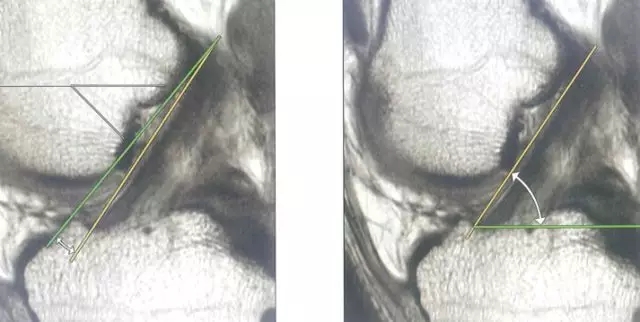

Blumensaat 角(-1.6度)

大于9-15度视为异常

前交叉韧带与胫骨平台角度(56度)

小于45-50度视为异常